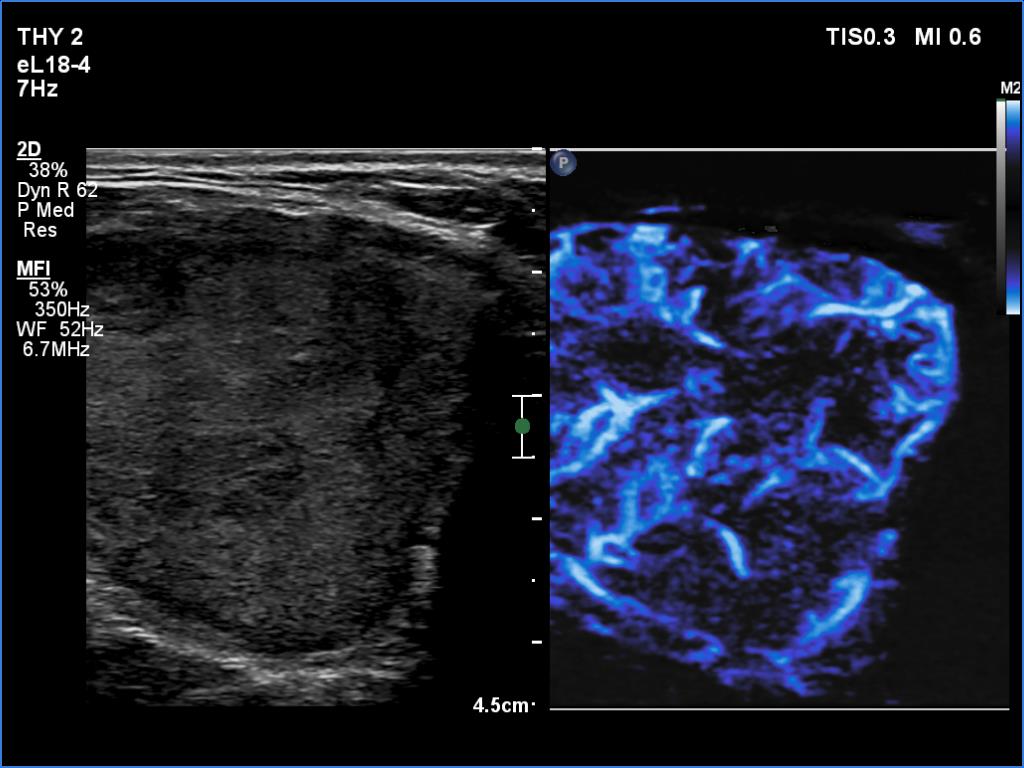

Right lobe, longitudinal scan

Medial part of the right lobe, transverse scan, microflow imaging. The nodule is rich in vessels.